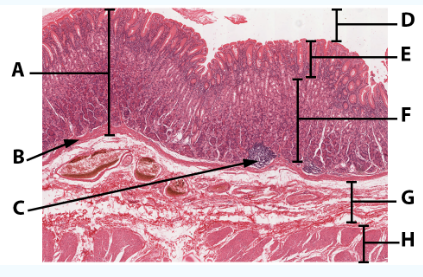

A

Mucosa

B

Muscularis mucosa

C

MALT

D

Lumen

E

Gastric pits: simple columnar epithelium

F

Gastric glands

G

Submucosa

H

Muscularis externa: oblique, circular, and longitudinal

area

Stomach